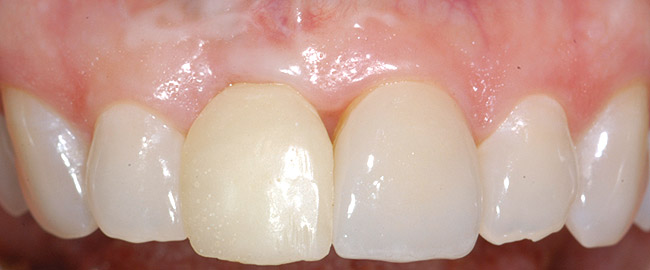

Treatment consisted of flapless extraction, socket grafting using mineralized bone allograft (Puros®, Zimmer Dental Inc, Carlsbad, CA), and a pedicled connective tissue graft36,37(Figure 11). Five months post-surgery, reentry was accomplished via a mid-crestal and labial sulcular incision. A crestal plasty was per- formed before implant placement into type II bone (Figure 12 and Figure 13). An immediate provisional was used for 3 months (Figure 14) before final crown fabrication (Figure 15).

Figure 14  Immediate provisional crown in place, 2 months after implant placement surgery. Please note gingival margin height of opposing lateral incisor (dotted line).

Figure 14

Figure 15  Completed crown. Note short distal papilla secondary to lack of appropriately placed point contact.

Figure 15